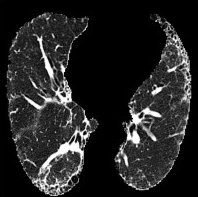

Based on Eqn. (2), we can identify the most influential cluster contributing to the final score for each individual by vectorizing the feature for each cluster. The heatmap in Supplementary Fig. 2 represents the contribution of the cluster to the final patient-level risk score on the FLD dataset, where the panels from left to right depict the vectors for patients arranged in decreasing order of value. The rationale behind each patient’s final prediction: the red cube highlights clusters contributing to high-risk scores, while blue indicates a lower risk. From this visualization, we can see that patients with different prediction results are highly disentangled, and the contributing patterns are clearly delineated for each patient. The most influential clusters across the dataset are determined by comparing the average values between the two classes with different predictions. The ranking of clusters by contribution to the ‘mortality in one year’ class on the FLD dataset is shown in Supplementary Fig. 3 and the most representative slice patterns are provided in Supplementary Fig. 4, which show that the model can identify common clusters within each class group, enabling us to pinpoint most significant features by visualizing the most frequently contributing clusters among patients.

Cluster 49